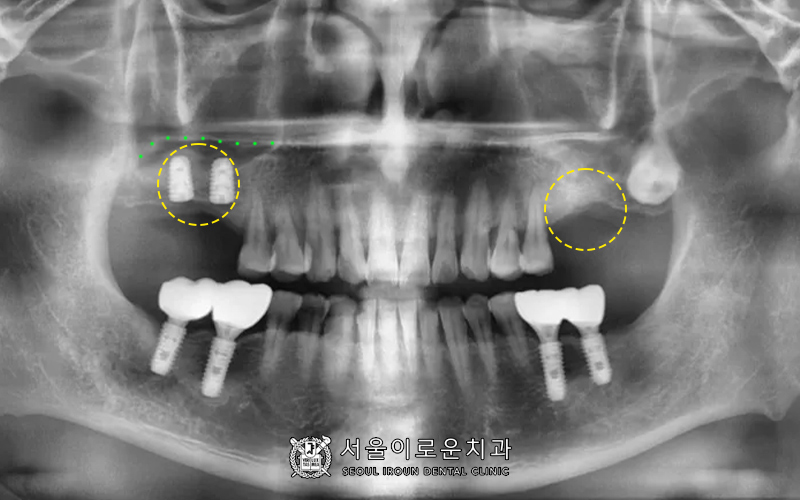

치료마무리 사진입니다 🙂

오른쪽 위는 고난도 임플란트인

상악동 거상술을 진행한 뒤

안정적으로 식립되어있는 것을

관찰할 수 있습니다 🙂

왼쪽 위 역시 뼈이식이 잘되었는데요.

bone이 안정적으로 확보되기까지

조금 더 기다린 뒤 임플란트를

식립하기로 결정하였습니다 🙂